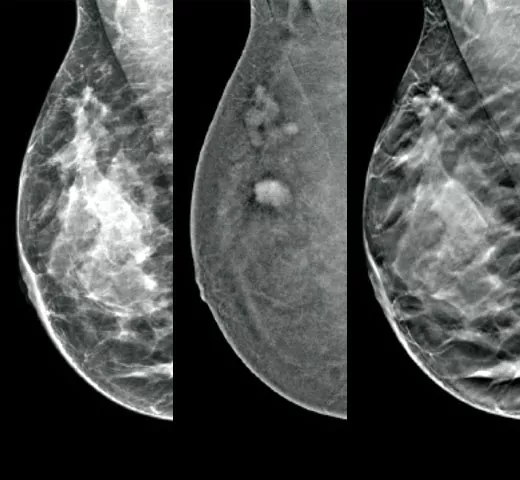

Clarity HD™ High Resolution Tomosynthesis

Producing high-resolution tomosynthesis images normally means slower read times. However, combining Clarity HD high-resolution 3D imaging with Genius AI Detection technology and 3DQuorum allows you to unleash fast and high resolution 3D images,5 accelerating screening and analysis.

Intelligent 2D™ Synthesised Imaging

For higher image quality, more detail, improved read times and low dose, this AI-powered software produces robust, yet natural looking, synthesised 2D images that are well correlated with the 3D mammography data. This enables radiologists to quickly and confidently see subtle mammography features and lesion morphology.

I-View® Contrast Enhanced Imaging

Turn the invisible into the visible with I-View 3-in-1 Contrast-Enhanced Imaging software. Leverage the ability to provide 2D, contrast-enhanced, and tomosynthesis images under one compression.9 This increases diagnostic confidence and helps guide the clinical pathway from diagnosis to surgical management.